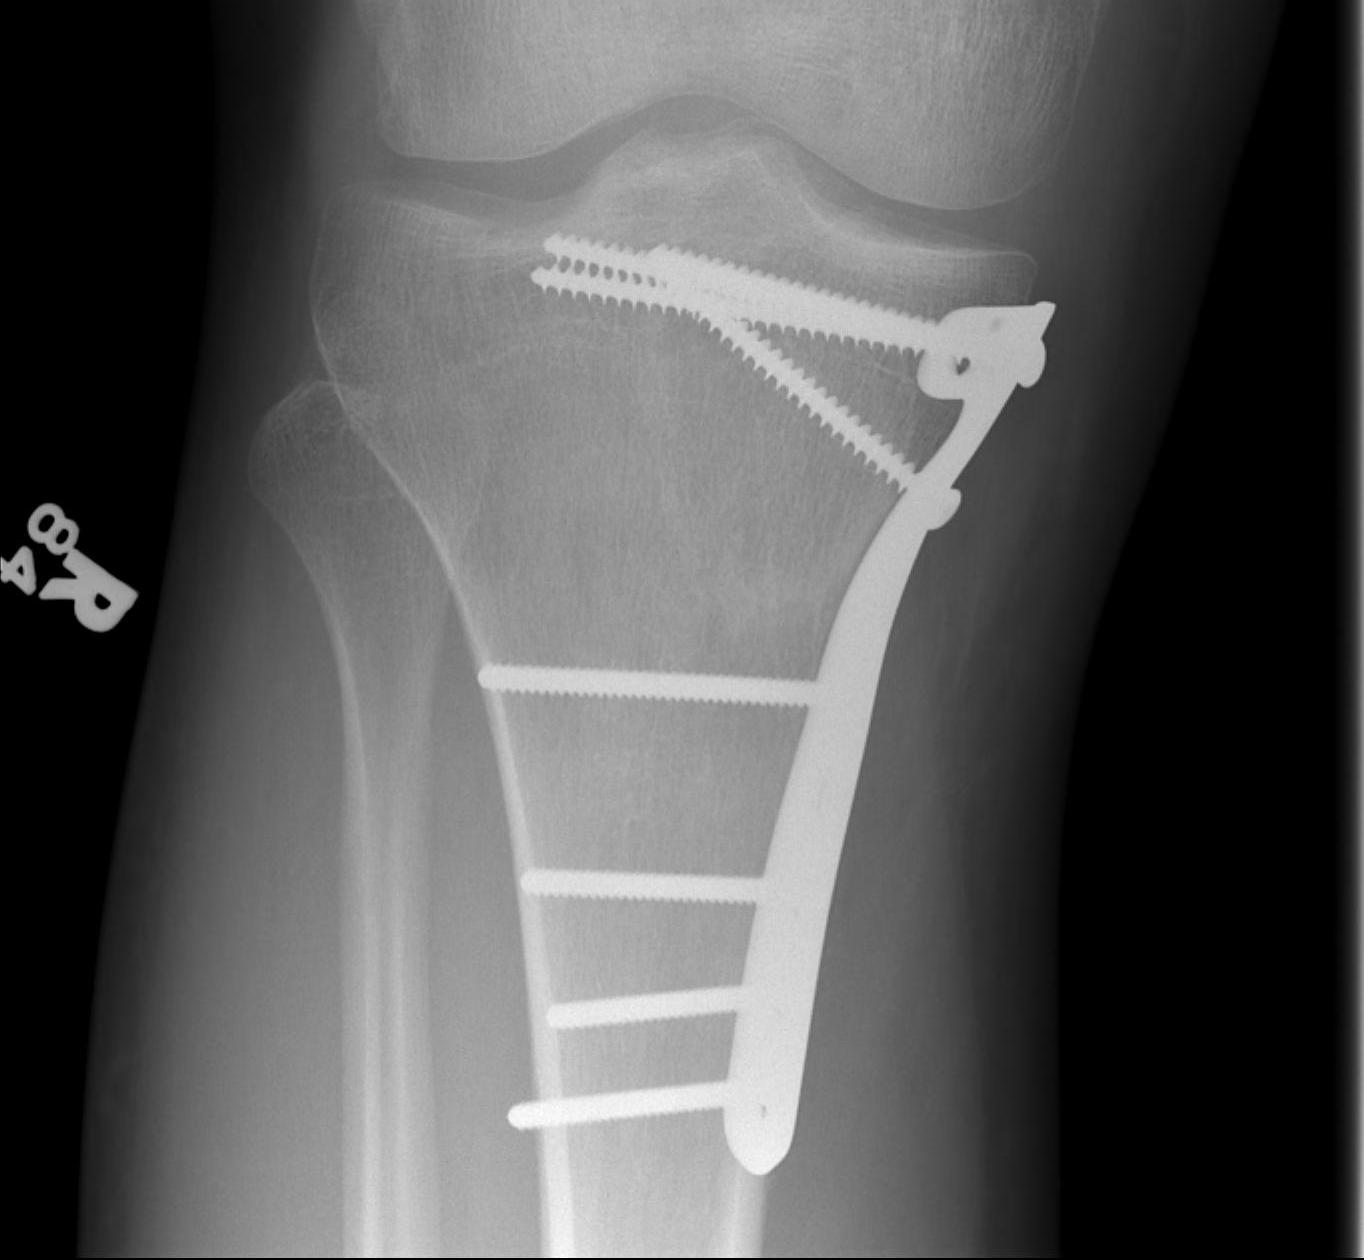

1. Medial and Lateral Plating

Technique

- depends on which of the three columns affected

- anterolateral approach for lateral column

- posteromedial appraoch for medial / posterior column

Type VI Bicondylar with Metaphyseal Fracture

- long locking plate minimally invasive with locking jig / MIPO

- proximal lag screws

- ensure correct alignment

- often use small medial buttress plate